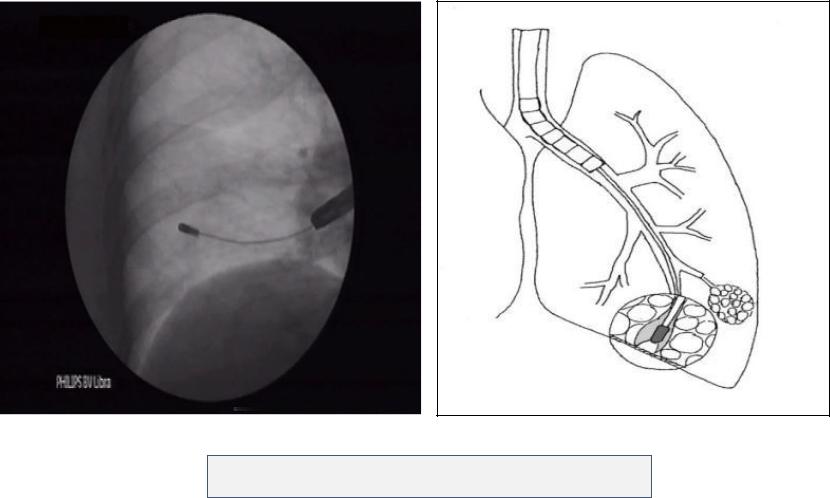

Криобиопсия: техника

Общее время – около 20 минут!

Криобиопсия: образцы